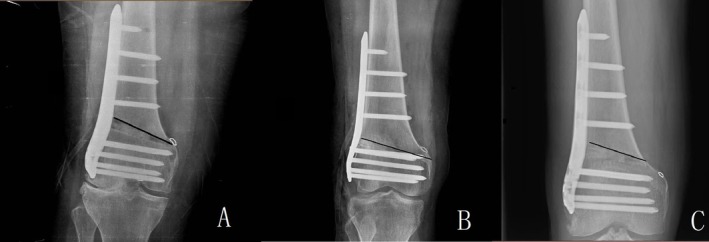

Objective: Hinge fracture is a known complication of lateral open wedge distal femoral osteotomy (LOWDFO). However, few studies have differentiated between intraoperative hinge fractures (IHF) and postoperative hinge fractures (PHF). This study aims to investigate the causes of these two types of fractures to help reduce complication rates and improve surgical outcomes.

Methods: We retrospectively analyzed data from 100 patients with genu valgum deformity and lateral unicompartmental osteoarthritis who underwent distal femoral osteotomy at our hospital between January 1st, 2022, and January 1st, 2024, in our hospital. Clinical parameters, radiological data, and the associated factors influencing IHF and PHF were analyzed. Radiological data such as mechanical axis deviation (MAD) and mechanical lateral distal femur angle (mLDFA) were collected. Clinical outcomes such as osteoarthritis index and time of healing were evaluated. Based on fracture morphology, IHF and PHF were further classified into Type 1 (extension), Type 2 (distal) and Type 3 (proximal) for detailed analysis. Statistical analyses included t-tests, Chi-square tests, and regression models to identify factors associated with IHF and PHF.